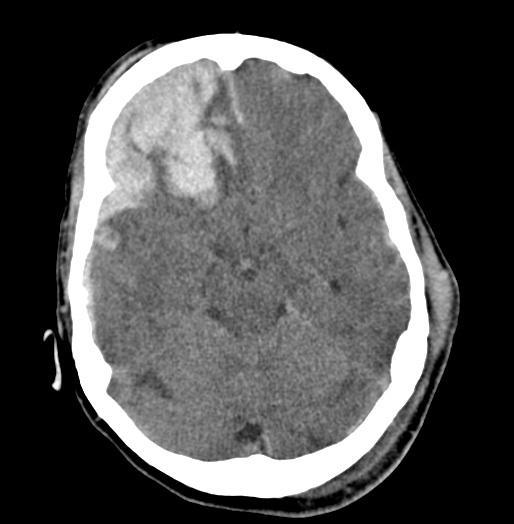

Multiple Brain Mets